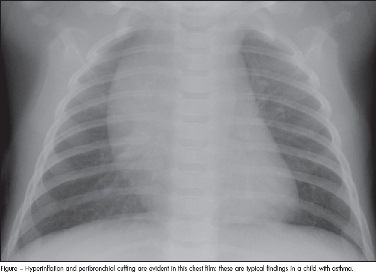

asthma

A chronic inflammatory disease of the airways, asthma is one of the most common reasons why children are brought to a physician. In this article, we outline a treatment strategy for the acute asthma flare....